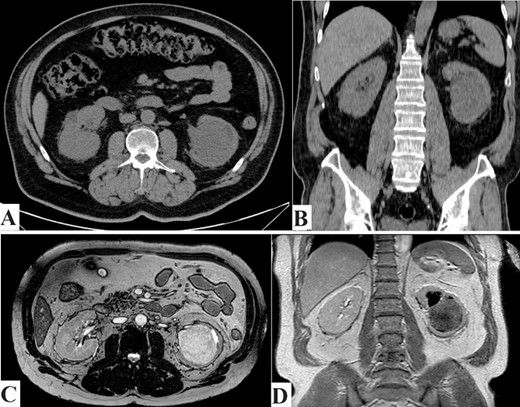

As part of his evaluation for his elevated serum creatinine, abdominal ultrasound showed the presence of a large, well-defined hypoechoic medullary lesion with internal heterogeneity and minimal vascularity measuring about 6.7 × 7.4 cm2 and abutting the inner aspect of the left renal cortex. Renal computed tomography (CT) scan without contrast demonstrated a well-defined rounded soft tissue density mass lesion measuring about 6.7 × 6.4 × 7.9 cm3 in the lower aspect of the left renal medulla (Fig. 1A and B).

(A) CT scan axial section and (B) CT scan coronal section. Showing left kidney well-defined rounded soft tissue density mass lesions measuring about 6.7 cm in the lower aspect of the renal medulla. (C) MRI axial section, and (D) MRI coronal section. Showing left kidney large well defined rounded hypointense on T1W and heterogenous hyperintense on T2W images focus seen in the lower aspect of the medulla of the left kidney measuring about 6.8 cm approximately, resulting in mild calyceal dilatation.

As the serum creatinine was elevated, preventing the use of contrast material with the CT scan, abdomen magnetic resonance imaging ‘MRI’ with gadolinium IV contrast showed a large, well-defined rounded lesion, hypointense on T1W and heterogeneous hyperintense on T2W image, with a focus seen in the lower aspect of the medulla of the left kidney measuring about 6.8 × 7.5 cm2 approximately, resulting in mild calyceal dilatation. After IV contrast administration, it showed mild heterogeneous enhancement, more marked in the delayed images. Two para-aortic small solid lymph nodes, the biggest measuring 1.2 cm, were detected. Chest imaging showed no evidence of distant metastasis (Fig. 1C and D).